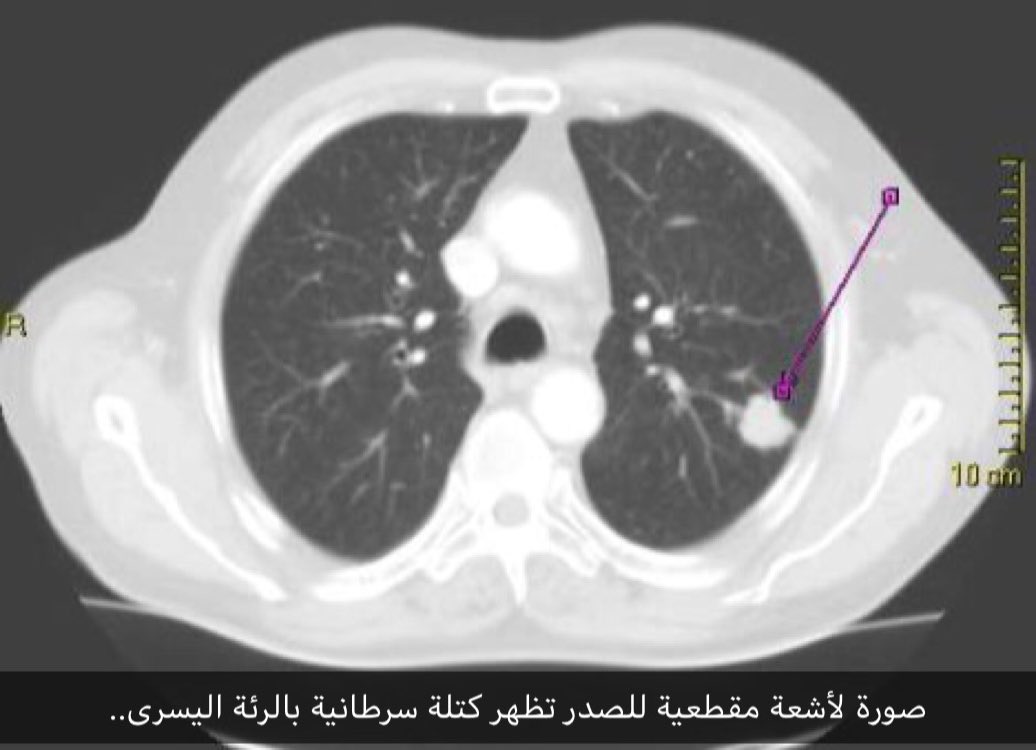

الاشعة المقطعية سرطان الرئة بالصور

محمد المشيقري Pa Twitter صورة أشعة مقطعية للصدر تختصر الكثيربالنسبة للعلاقة بين التدخين و سرطان الرئة بينما يظهر الورم السرطاني السهم الأسود في الرئة تظهر علبة السجائر و الولاعة السهم الأبيض في

نتائج المقطعية لكشف سرطان الرئة